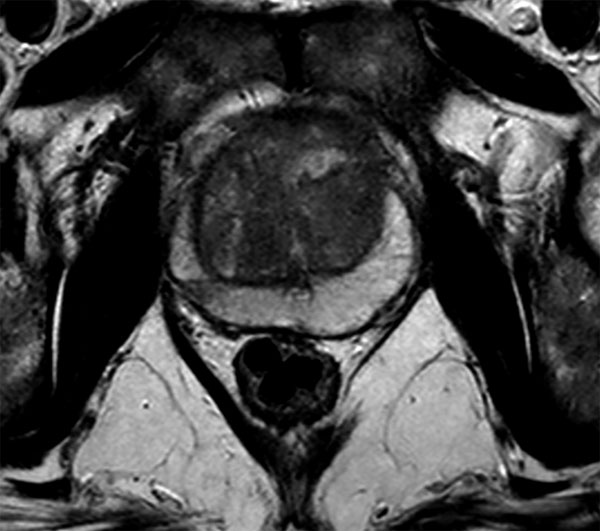

Axial T2w TSE